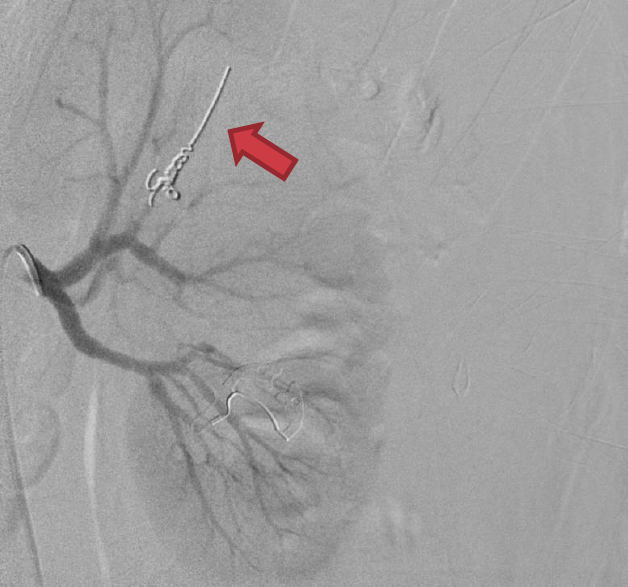

Angioembolisation

Angioembolisation in renal trauma is effective in selected patients.

Trauma CT: Blue arrow is contrast ‘blush’=active bleeding point. Red arrow is perinephric haematoma.

When transferring these patients from smaller hospitals to larger centres, consider whether initial destination should be the ED for rapid re-assessment prior to entering IR suite.